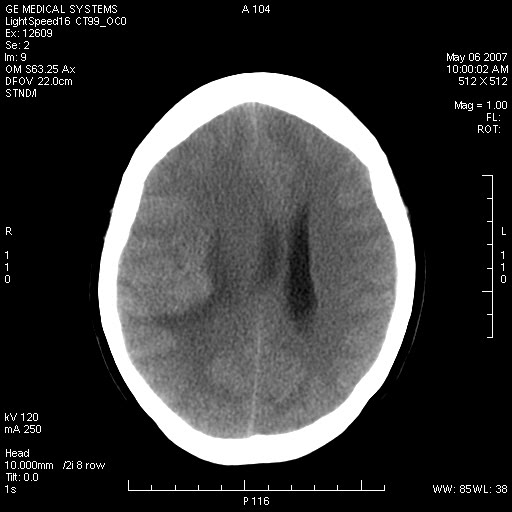

女,60岁,头痛6~7天。

右颞叶巨大高低混杂密度肿块,病灶内可见多发条块状钙化影,占位效应明显,中线结构显著左偏,肿块周围水肿明显,临近颅骨吸收变薄,边缘光整,考虑1少枝胶质瘤2脑膜瘤3转移瘤4室管膜瘤5淋巴瘤6三叉神经瘤(多多益善)合并镰下疝

右颞叶混杂密度,累及右额叶。其内可见条片状钙化及斑片状略高密度,周围少量水肿,右颞骨吸收变薄,中线结构左移。考虑1少突胶质瘤。2脑膜瘤。合并瘤卒中。建议增强扫描。

右额、颞叶巨大高低混杂密度肿块,病灶内可见多发条块状钙化影,占位效应明显,中线结构显著左偏,肿块周围水肿明显,临近颅骨吸收变薄,边缘光整。

考虑:1、少枝胶质瘤;

2、脑膜瘤?

3、镰下疝;

4、建议增强扫描进一步检查。